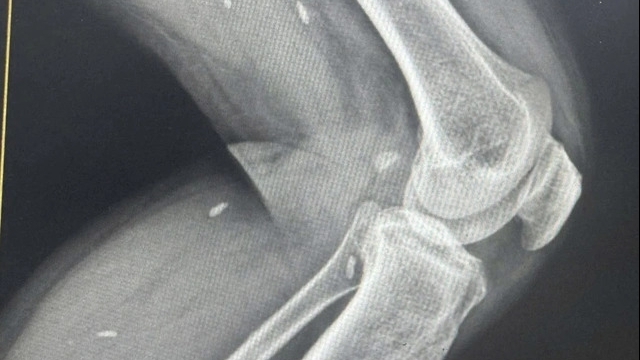

Ngày 30/8, khi thấy ông T. diễn biến nặng lên, đau đầu và mệt mỏi nhiều, gia đình chuyển ông đến Bệnh viện đa khoa tỉnh cấp cứu. Với kết quả xét nghiệm nghi ngờ và có hình ảnh tổn thương phổi, ngày 1/9, bệnh nhân được chuyển lên Bệnh viện Bệnh nhiệt đới trung ương để điều trị trong tình trạng suy hô hấp nặng, phải thở máy.

Bệnh nhân 1045 có nhiều bệnh lý nền như phì đại tiền liệt tuyến và thoát vị cột sống cổ. Hiện tại, phổi bệnh nhân tổn thương nặng, kềm thêm bội nhiễm các vi khuẩn khác ngoài SARS-CoV-2.